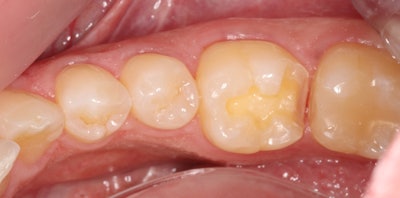

The CEREC Primescan system (Dentsply Sirona) was used for same-visit digital dentistry, starting with a digital impression, which was then used to design the restoration. Shade A2 was selected for the Avencia block, which milled in approximately 4.5 minutes.

Next, after removing the sprue, the restoration was steamed to remove the lubricant used in the milling process, after which it was seated to verify distal contact.

After verifying fit during try-in, the restoration was removed and polished for about 45 seconds at no more than 4,000 rotations per minute (rpm) using a Meisinger Twist Polisher for hybrid blocks.